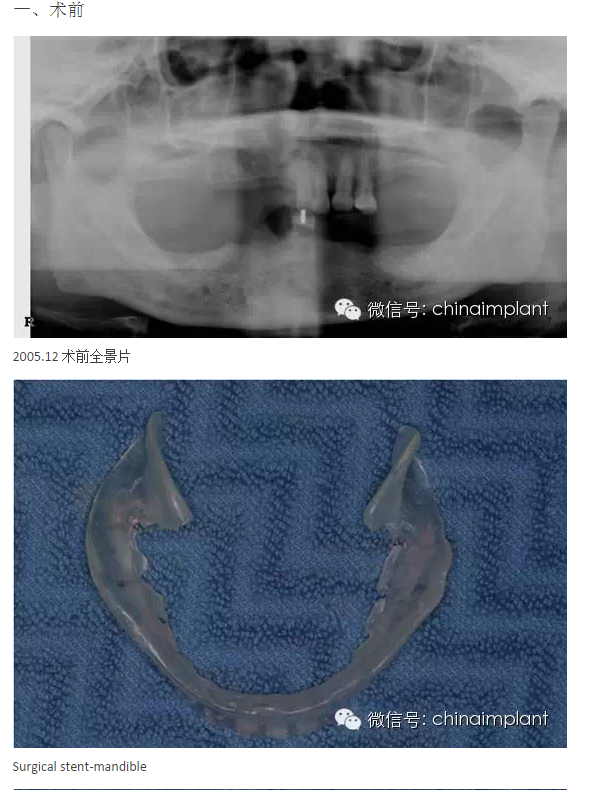

之前針對(duì)全口無(wú)牙進(jìn)行種植修復(fù)的案例中,因?yàn)轭M骨的原因,后期使用橋冠修復(fù)時(shí),一般是3部分(兩側(cè),磨牙,前牙),最近的案例中修復(fù)是一般都是做一體式的橋冠,現(xiàn)在從臨床的修復(fù)案例來(lái)看,沒有什么問(wèn)題。

本案例已經(jīng)將近10年了(2005年12月),但是修復(fù)效果個(gè)人認(rèn)為很不錯(cuò),所以拿出來(lái)和大家分享。